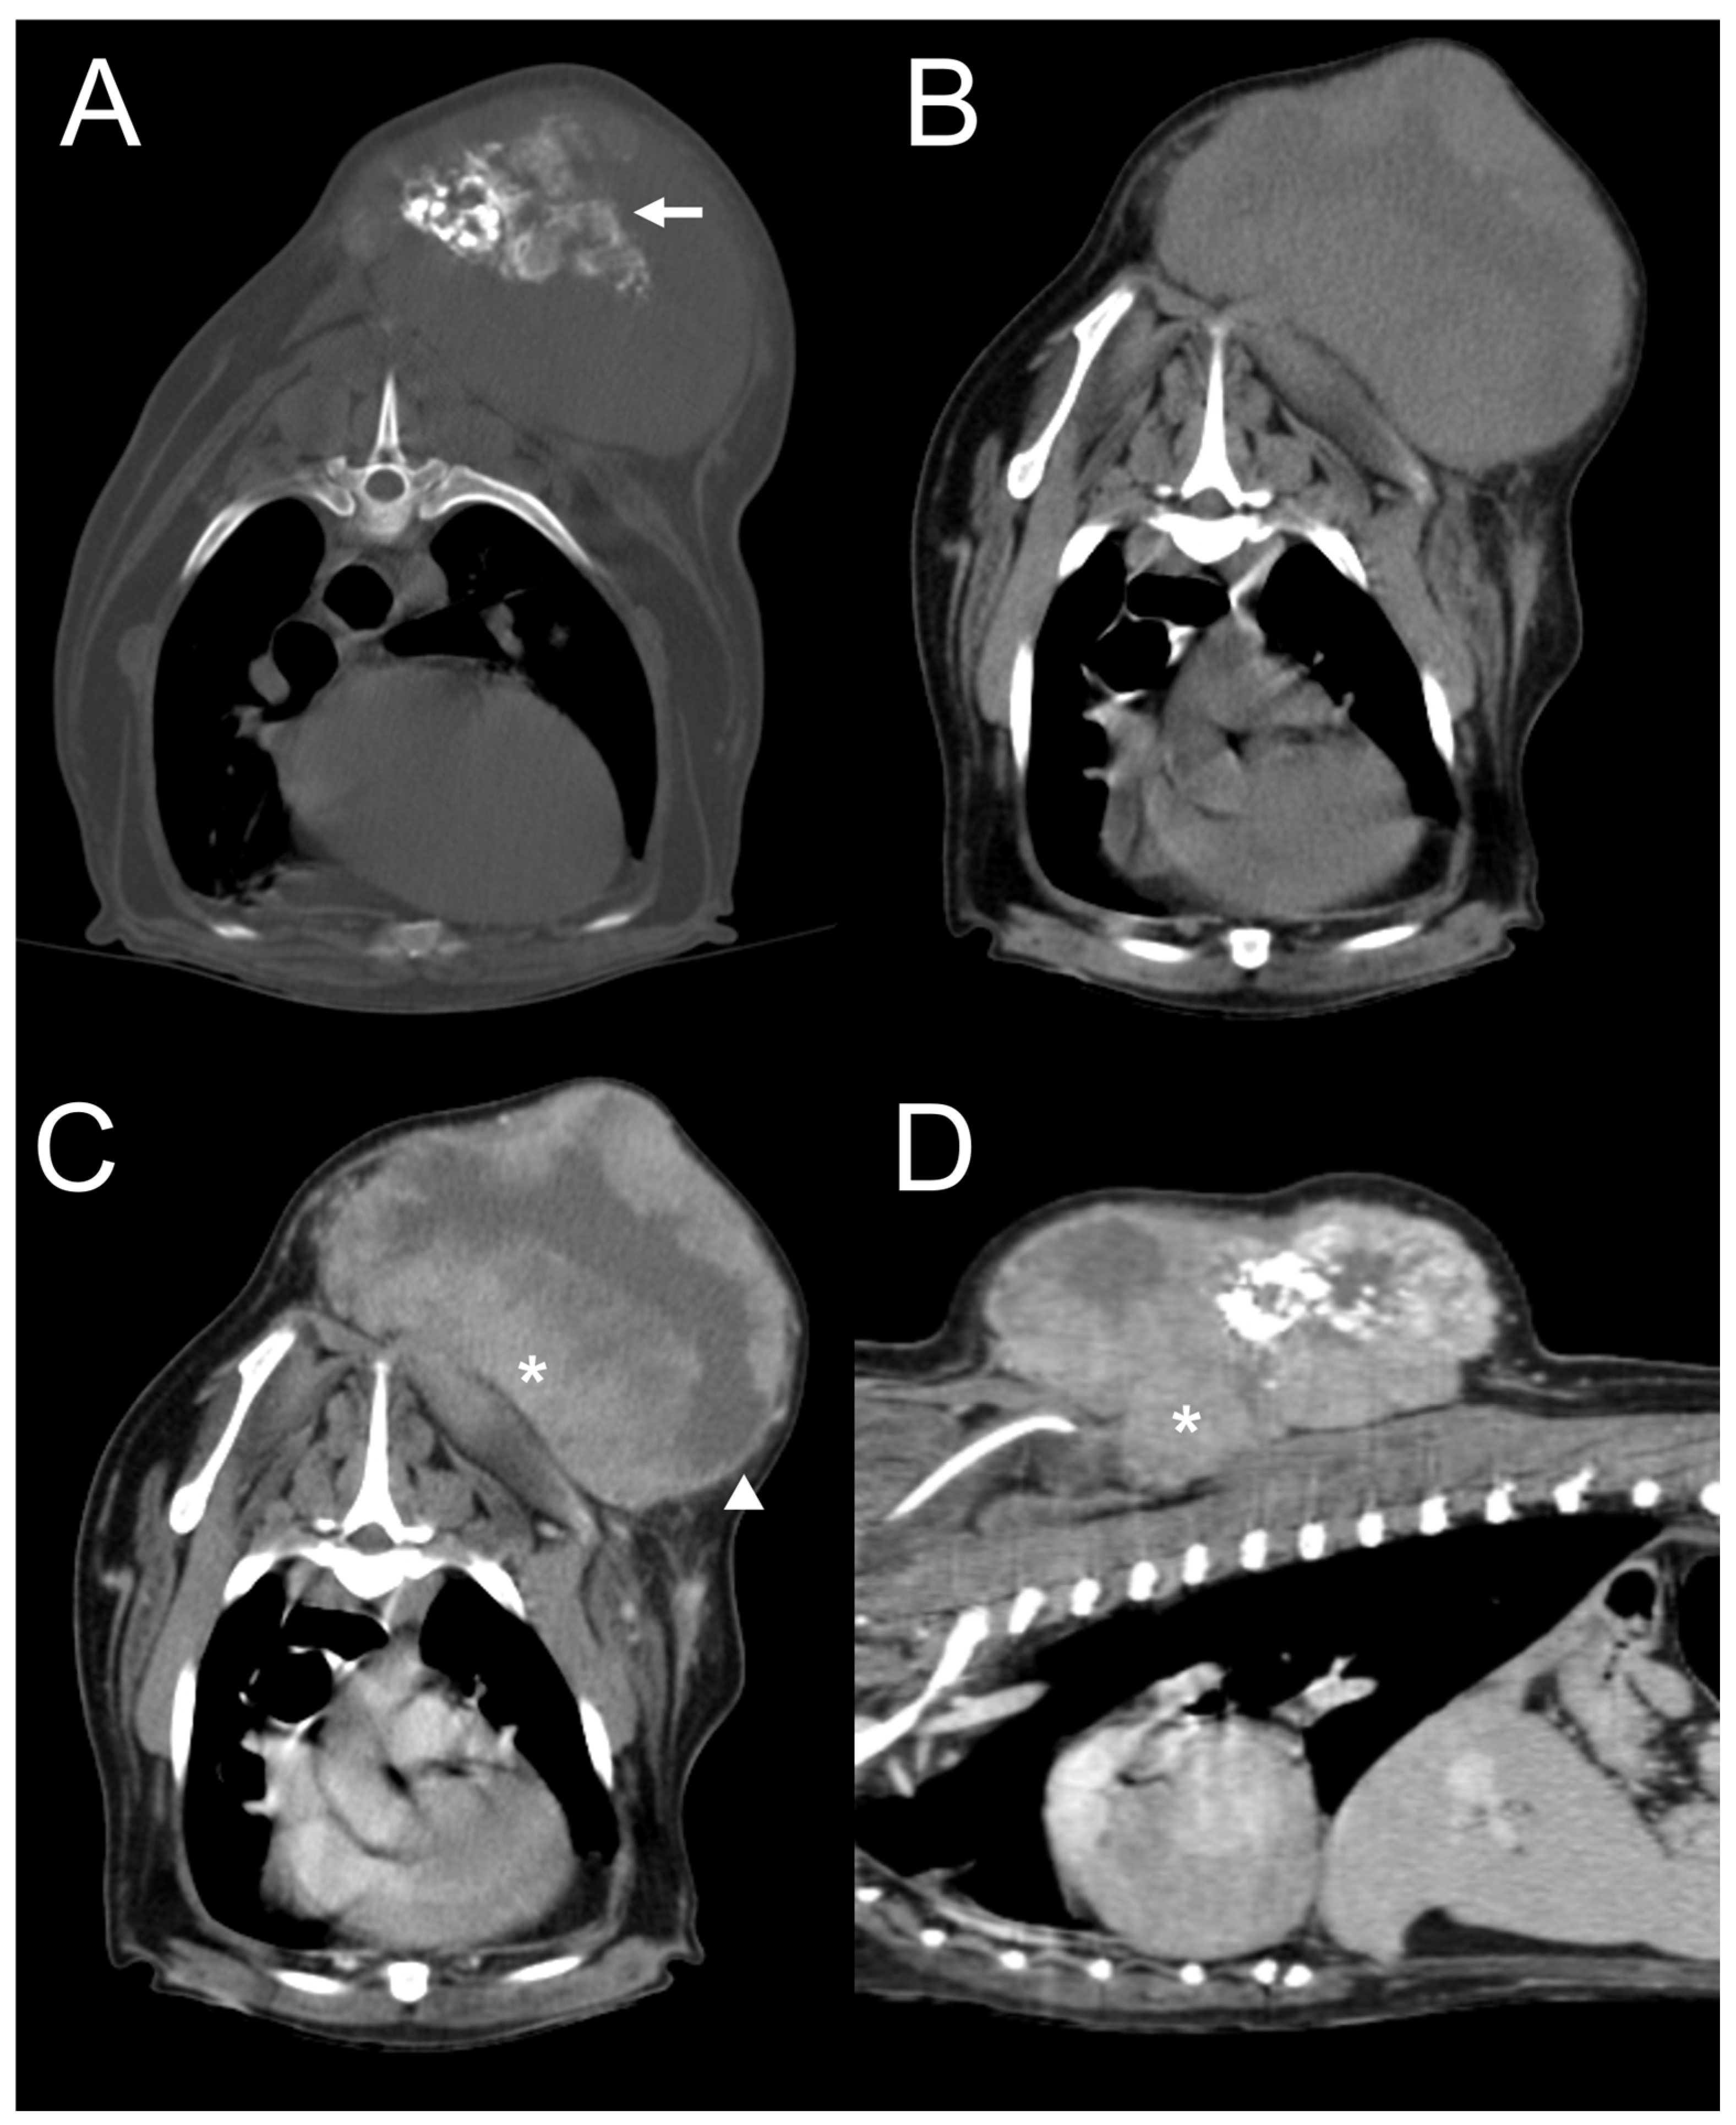

| Dog 1 | Subcutaneous (right parotid) | Ill-defined | Heterogenous | Absent | Present | Marked | Amorphous | Mixed |

| Dog 2 | Subcutaneous (right forelimb) | Well-defined | Absent | Present | Present | Moderate | Spindle | Mixed |

| Dog 3 | Subcutaneous (dorsum at level of the 4th–5th cervical vertebrae (C4–5)) | Ill-defined | Heterogenous | Absent | Present | Moderate | Amorphous | Mixed |

| Dog 4 | Subcutaneous (dorsum at the level of the 1st–8th thoracic vertebrae (T1–8)) | Well-defined | Heterogeneous | Present | Present | Moderate | Amorphous | Mixed |